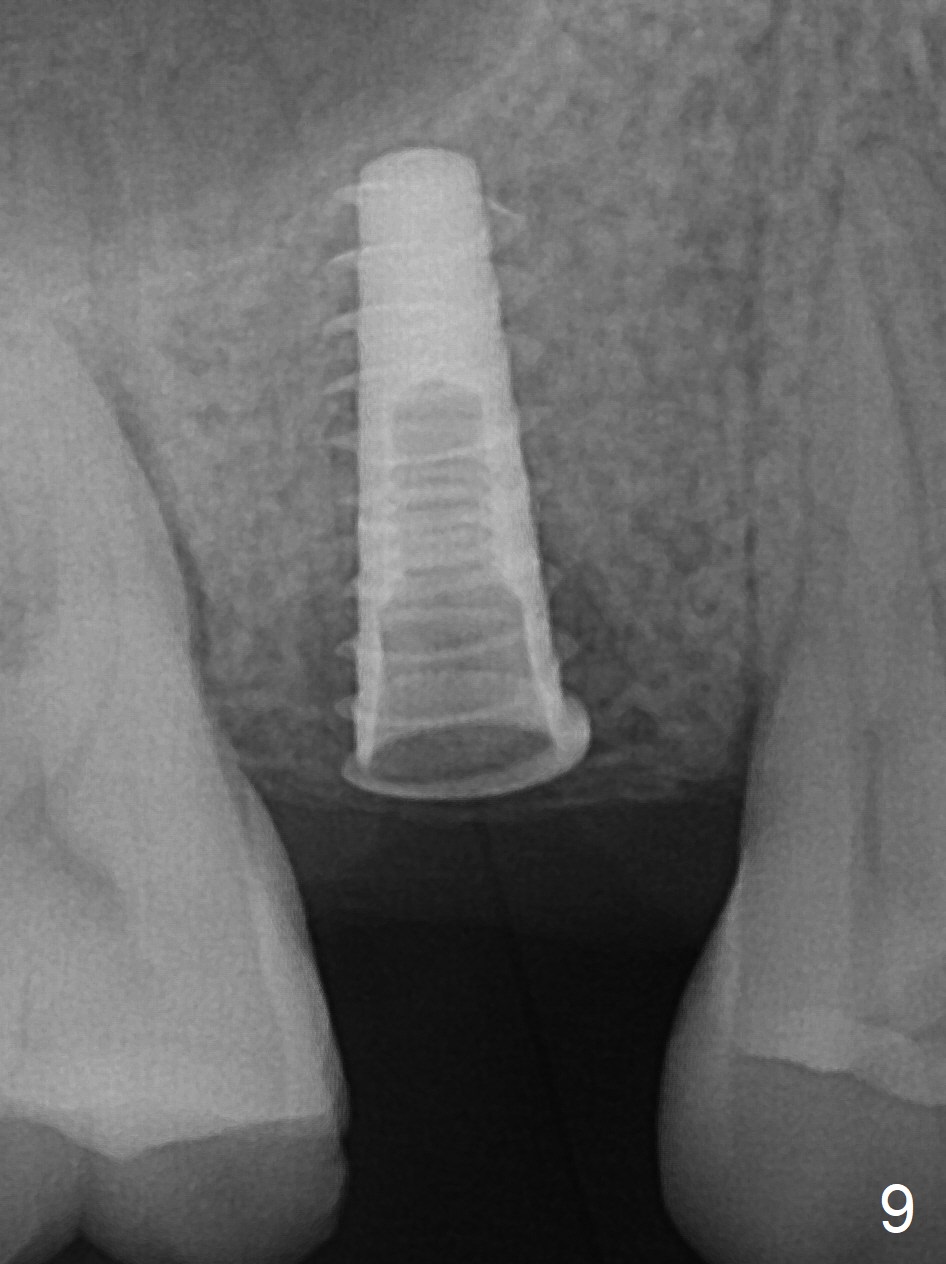

A 47-year-old man returns emergently with subgingival fracture of the lingual (L) cusp of the tooth #4 (Fig.1-3). After extraction (no bony defect) without drilling, a 4x11 mm dummy implant is placed as a tap drill with satisfactory stability (Fig.4,5). To get subcrestal placement, a shorter (4x9 mm) implant is inserted with insertion torque of < 35 Ncm. In retrospect, a larger implant (4.5 mm) would be better in term of primary stability. After allograft placement into the buccal and lingual gaps, a 4.5x4(4) mm abutment is placed for an immediate provisional. There is a peri-implant gap 7 months postop (Fig.7<, as compared to the implant at #2 (6 months postop)) . When the loose abutment is being retightened, the patient feels pain, although the gingiva appears healthy (Fig.8). A larger implant should have been used; the abutment should have been removed. The implant dislodges while the abutment is untightened 8 months postop. The osteotomy is found intact. A 4.5x11 mm dummy implant is placed 2 mm subgingival with 20 Ncm (Fig.9). When a 4.5x11 mm definitive implant is placed 3 mm subgingival (Fig.10,11), torque reaches 50 Ncm. A 5.5x3 mm healing abutment is placed. Three months postop, the implant is stable (Fig.12,13) and impression is taken.